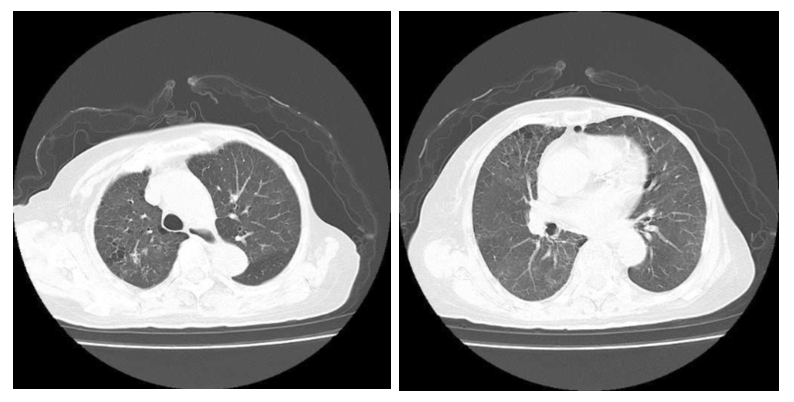

患者经验性抗感染治疗后症状进行性加重,仍诉咳嗽咯血,胸闷气促,无发热。氧合指数进行性下降(最低值102),经会诊后于2022-03-24转入ICU,予经鼻高流量氧疗(FiO2: 90%,流速50 L/min)。复查血常规:WBC 8.57×109/L、HGB 69.00 g/L、PLT 141.00×109/L。CRP 90.14 mg/L,PCT 0.44 ng/mL,IL-6 211.40 pg/mL。Scr 141.43μmol/L、UA 372.60 μmol/L、BUN 12.87 mmol/L。凝血功能:D-二聚体0.57 μg/mL、余正常。心肌酶谱和肌钙蛋白正常,核周型抗中性粒细胞胞浆抗体(典型)阳性、抗核抗体(ANA)强阳性、ANA滴度1∶320(正常参考值< 1∶100),天然SS-A抗体强阳性、抗Ro-52抗体强阳性、抗SS-B抗体强阳性,抗心磷脂抗体阴性。血气示:pH 7.388、PaCO2 32.6 mmHg、PaO2 77.9 mmHg(FiO2 90%)、BE-5.4 mmol/L、HCO3- 19.6 mmol/L、Lac 1.6 mmol/L。支气管镜灌洗液呈血性,提示大量含铁血黄素组织细胞。3次痰培养抗酸染色、革兰氏染色阴性,2次血和痰培养未见细菌和真菌。胸部DR:两肺见广泛片絮状高密度影,右肺见片状实变影,较前明显进展(图 2A)。结合患者胸片和肺部CT表现,考虑急性重症狼疮性肺炎,弥散性肺泡出血。停美罗培南,改用哌拉西林他唑巴坦钠(4.5 g, ivgtt, q8h)+伏立康唑(0.2 g, ivgtt, q12h)+SMZ(2片,po,q12h)预防院内感染、真菌感染及非典型病原体感染,继续予甲泼尼龙静脉注射(40 mg,qd)治疗。

| A:2022-03-24检查示两肺见广泛片絮状高密度影,右肺见片状实变影,较2022-03-22前明显进展;B:2022-03-29检查示双肺见散在片絮状高密度影,双侧肋隔角锐利,较022-03-24明显改善 图 2 患者胸部DR检查影像 |

患者仍然诉胸闷,呼吸窘迫、咯血,伴有血色素进行下降,2次粪便隐血试验阳性。患者既往有股骨头坏死和肿瘤病史,拒绝激素冲击和免疫制剂治疗。为尽快改善症状,行血浆置换术(3 000 mL,qd),继续维持甲泼尼龙原治疗,加强护胃。经过连续5次血浆置换后,呼吸困难、咳嗽明显改善,无咯血。2022-03-29患者高流量吸氧改为普通吸氧,3.0 L/min,各项检查值:SaO2 97%~99%,WBC 8.16×109/L、中性粒细胞计数(NEUT)7.56×109/L、HGB 82.00 g/L。CRP 7.06 mg/L,IL-6 4.10 pg/mL,PCT 0.16 ng/mL,ESR 15.1 mm/h,Scr 111.20 μmol/L,总胆红素(TBIL)26.62 μmol/L、白蛋白(ALB)39.32 g/L、肝功能、电解质正常。核周型抗中性粒细胞胞浆抗体(典型)弱阳性、抗核抗体(ANA)强阳性、ANA滴度1∶100,天然SS-A抗体弱阳性、抗Ro-52抗体弱阳性、抗SS-B抗体弱阳性,抗心磷脂抗体阴性。胸部DR提示:双肺见片絮状高密度影,较前改善(图 2B)。2022-03-31复查胸部CT提示:双肺见多发磨玻璃样及片状高密度影,部分实变,较前吸收好转(图 3)。患者自动出院,出院口服泼尼松(40 mg,1次/d)和羟氯喹(200 mg,2次/d)治疗,并序贯减量,出院后2周(见附图 1A和图 1B)以及第6周胸部CT(见附图 1C和图 1D)随访较前进一步改善。